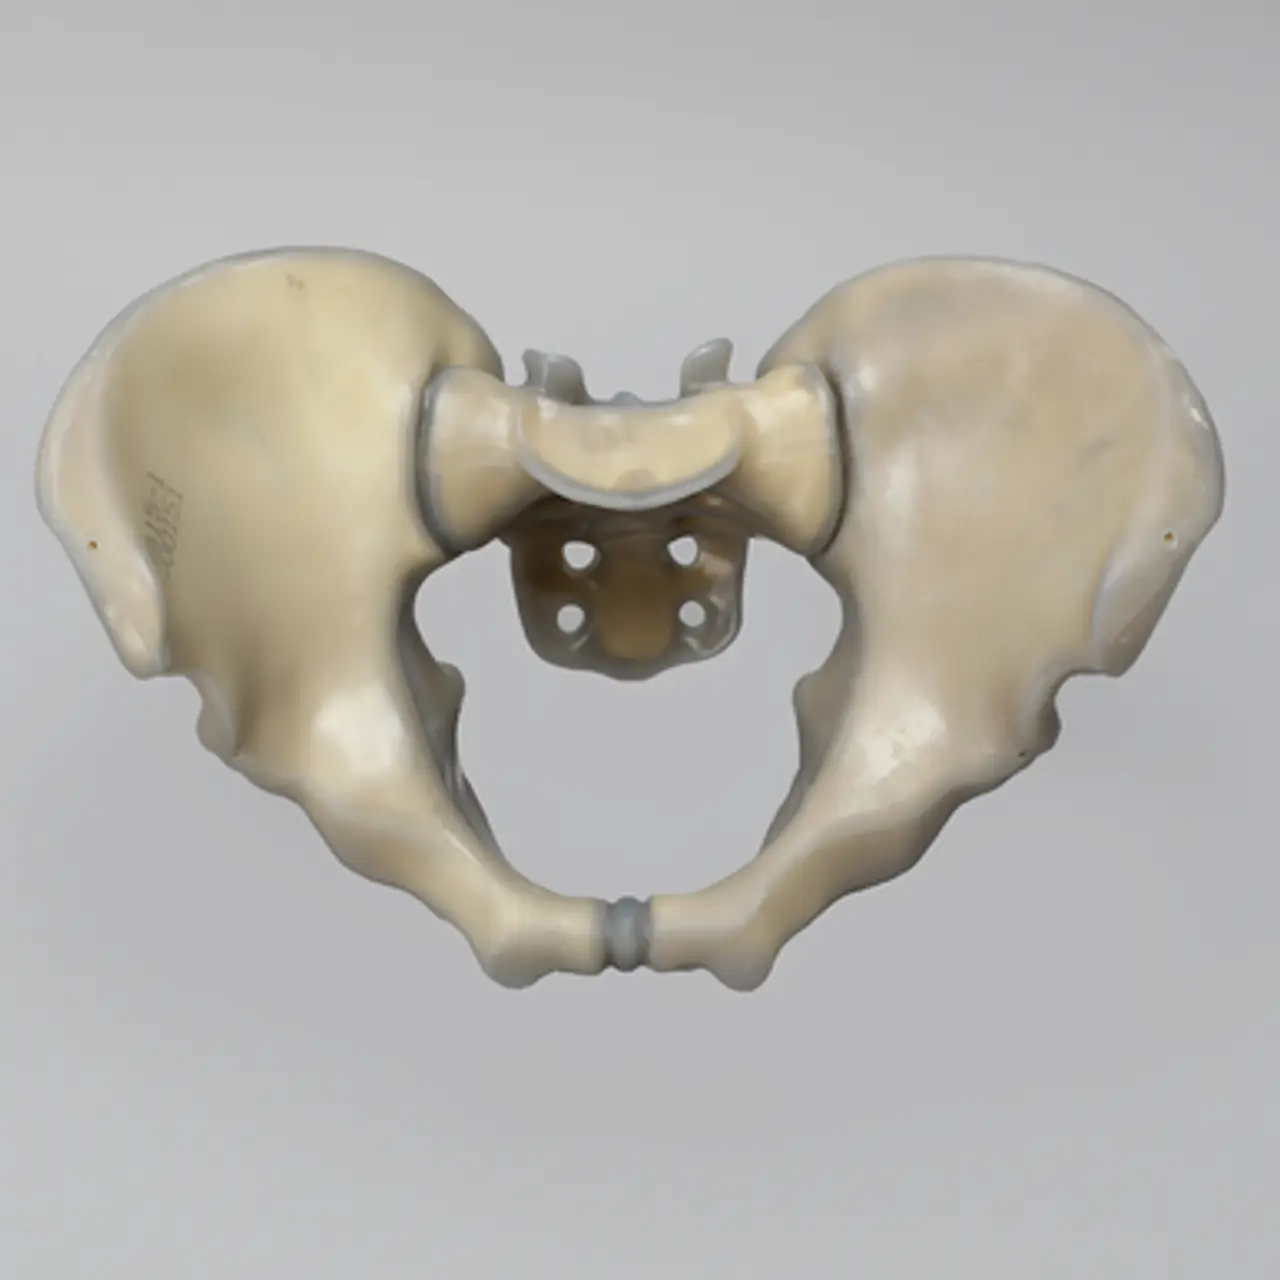

人工骨骨盆模型3415

人工骨模型,完整男性骨盆,absolute™ 第四代,17 PCF 实心泡沫芯,大号

用于力学测试的完整男性骨盆

我们的 absolute™ 骨模型 精确模拟人体骨骼的结构与力学特性,能够帮助科研人员和医疗器械企业在开发与审批过程中,轻松且经济地再现载荷与运动场景。该模型特别适用于生物力学研究、医疗器械测试及教学演示。

| 解剖部位 (Anatomy) | 骨盆 – 完整 |

| 模型类型 (Model Type) | absolute™ 骨模型 |

| 材料 (Material) | absolute™ |

| 尺寸 (Size) | 大号 |